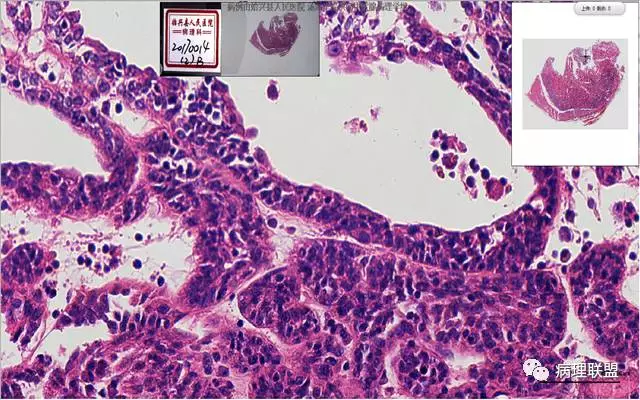

患者,女,45岁,发现双侧甲状腺肿物半月余。大体所见:左侧甲状腺肿物:4.3*5*4cm肿物一个,包膜完整,光滑,质脆,中央见出血。右侧甲状腺组织:3*1.6*1.5cm及1*1*0.8cm组织两块,其中较大的组织切开见内有0.8cm及1.2cm两个,质硬,灰白色,界不清,较小的,切开见灰黄色,质脆。